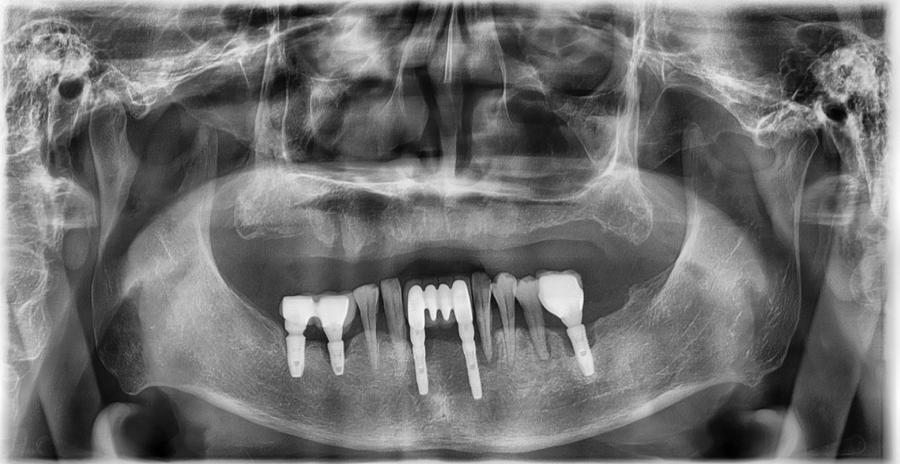

Through panoramic X-rays and oral scans,

we checked the current gum height, gum thickness,

and even the movement of the jaw.

Because there were no teeth at all in the maxilla to provide support,

• There were no remaining teeth in the maxilla (upper jaw),

so a full denture was needed